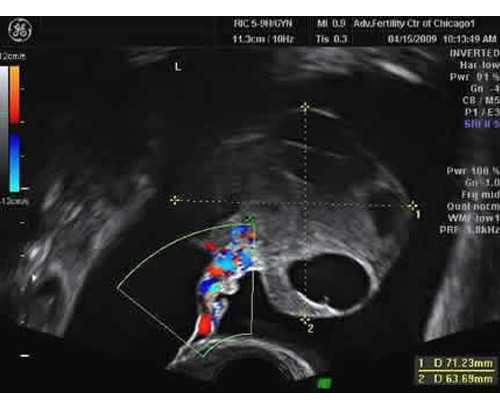

1.B超确定怀孕满6周以上,且有胎心胚芽(胚芽到达3mm以上)

B超结果出来了,一切都正常,但可能出现三个结果(我们按照7周检测要求的胚芽10mm来说明):

1、胚芽长度达到10mm了

胚芽长度已经发育到10mm(1cm)以上,宫内早孕,有胎心胎搏动。恭喜恭喜!胚胎发育正常,没有宫外孕的危险。达标了,所以您随时可以做检测了。

2、胚芽长度还不够10mm

明明50多天了,明明都已经7周了,为什么B超结果看到胚芽长度还不到10mm,有时候只有4mm?

没关系!排卵晚、胚胎着床晚都可能影响发育周期,只要看到胚芽了,就会有胎心胎搏动了,那么至少胚胎发育已经6周了。不要着急!过多几天就能抽血检测了(具体采血时间专业顾问会根据胎儿发育情况进行推算)。

3、没有胎心胎搏没有胚芽

这种情况在50多天存在的话,建议十天后复查B超,若还没胚芽胎心的话,请到医院就诊并听从医生建议。